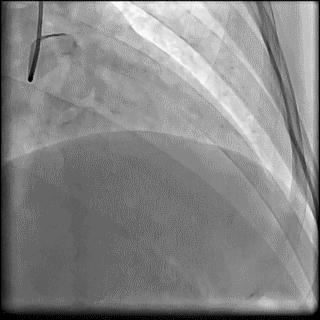

(4)LIMA桥血管造影

首选导管:JR4.0导管

其他导管:如果开口明显成角应选用专用的内乳动脉造影导管

➢ CASE 6

经股动脉途径TIG,非选择造影如果能清晰显影,可不做超选造影

➢ CASE 7

经左侧桡动脉途径JR4.0,非选择造影如果能清晰显影,可不做超选造影